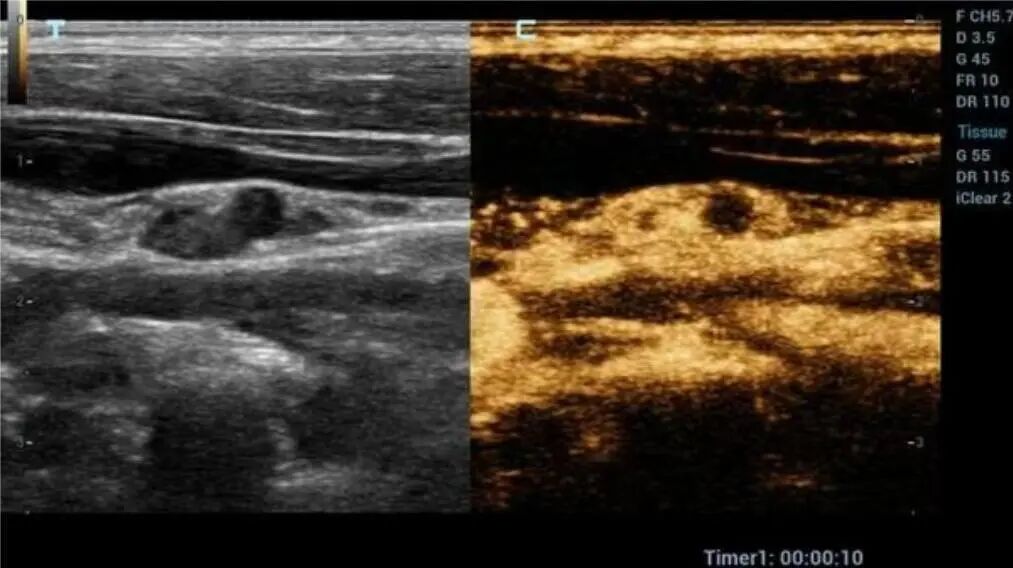

您是否也遇到过这些尴尬时刻?提重物时突然漏尿、运动时总觉下腹坠胀、更年期后总想跑厕所......这些信号可能在提醒:盆底肌需要关爱了。 盆底肌群如同"弹簧床",承托着膀胱、子宫等器官。妊娠分娩、雌激素变化、长期腹压增加等因素,都可能导致这张"网"松弛。若不及时干预,可能发展为: ▷ 盆腔器官脱垂(子宫/阴道膨出) ▷ 压力性尿失禁(咳嗽/大笑漏尿) ▷ 排便障碍(便秘/失禁) ▷ 性生活质量下降 【哪些人需要关注盆底筛查?】 ✓ 产后42天妈妈(尤其经阴道分娩) ✓ 频繁漏尿或排尿困难 ✓ 长期便秘/慢性咳嗽 ✓ 更年期女性 ✓ 性生活疼痛或下腹坠胀人群 【无创筛查新选择:盆底超声】 不同于传统指检,这项技术通过会阴体表扫描: ⏩ 多维度观察静息/收缩/用力状态 ⏩ 精准评估肌群损伤程度 ⏩ 动态捕捉器官位移情况 女性盆底三维多层显像 【检查须知】 ✔️ 避开经期 ✔️ 检查前排空膀胱 ✔️ 穿宽松裤装更方便 ✔️ 配合医生指令做缩肛/屏气动作 盆底超声检查 女性健康管理不该止于体检常规项。建议存在相关症状的女性,及时到正规医院妇产科或超声科咨询。早筛查、早干预,让盆底肌恢复应有的"托举力"。 注:部分图片来源于网络,如有侵权,请联系删除。 贵州航天医院超声科专家团队 吴艳辉 中共党员,超声科学科带头人、主任,主任医师 专业擅长:从事超声诊断工作约30年,对心血管、小器官超声、超声引导下介入等具有丰富的临床经验。 胡大海 超声科副主任,副主任医师 专业擅长:从事超声工作17年,对心血管、外周血管、浅表器官超声诊断等具有丰富的临床经验。 骆科美 中共党员,超声科副主任医师 专业擅长:从事超声诊断工作33年,对胎儿心脏及颅脑、妇产超声诊断、盆底超声等诊断具有丰富的临床经验。 刘 敏 超声科副主任医师 专业擅长:从事超声诊断工作20余年,对妇产科超声、心脏血管超声诊断具有丰富的临床经验。 贵州航天医院超声科简介 基本情况 贵州航天医院超声科配备多种超声检查设备(飞利浦彩超(IU-22、IU-Elite、HD11、Q5、Q7),迈瑞超声I9、DC-6、DC-8、GE-E8及床旁机,彩色超声诊断仪等),设有心血管诊室、妇产科诊室、腹部诊室、绿色通道、浅表小器官等检查室。 诊疗范围 科室业务覆盖腹部、泌尿、妇科、产科(常规、NT筛查、III级筛查超声检查及高危妊娠监护)、成人心脏、外周血管、浅表器官(包含甲状腺、乳腺、阴囊、眼睛等)、颅脑(小儿颅脑、成人颅脑)、小儿肺超、造影、盆底、腹直肌、肌骨神经等检查及各种介入引导。 专科特色 四肢血管超声检查、双胎产前筛查及超声监护、超声造影检查技术、介入超声临床应用、经颅脑实质超声辅助筛查诊断帕金森病、女性性早熟超声诊断、盆底超声检查等。 NT超声检查 超声介入引导 肝脏超声造影 甲状腺造影 颅脑超声帕金森辅助检查 乳腺超声造影 上肢动静脉造瘘超声检查 双胎超声筛查 下肢血管超声检查 右心造影 END